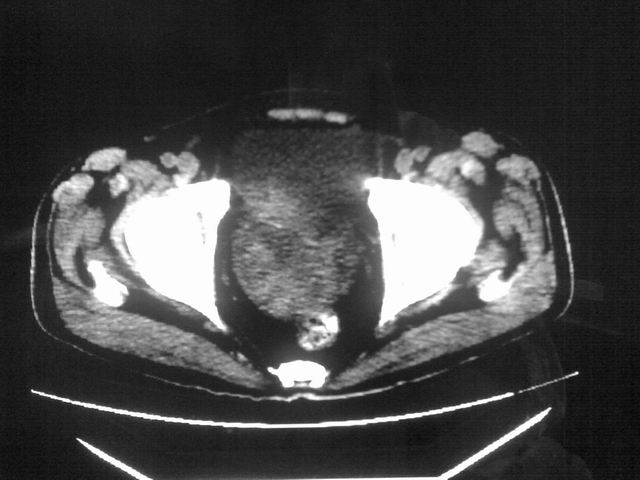

患者m 56岁,盆腔及下腹部胀痛半年,加重1月余,消瘦\中重度贫血.(附:平扫时直肠的高信号为,残留的钡剂).补一下病史:胃镜及纤维结肠镜均无明显异常.

首先是病灶的定位,平扫看很象肠管肿瘤但既然纤维结肠镜正常就可以除外结肠病变,增强成不均匀强化,位于右下腹部应该首先考虑回肠末段占位性病变,1淋巴瘤,2间质瘤,3腹膜后神经原肿瘤待除外,

膀胱后方及直肠前方见巨大混杂密度影,与前列腺相连且向膀胱内突入,精囊腺显示不清;考虑前列腺癌侵犯精囊、膀胱。

膀胱及直肠间有不规侧的软组织密度影,内密度不均匀。其内有坏死囊变,前列腺及精囊腺,膀胱后壁受浸。结合病史考虑腹膜后肉瘤可能性大。